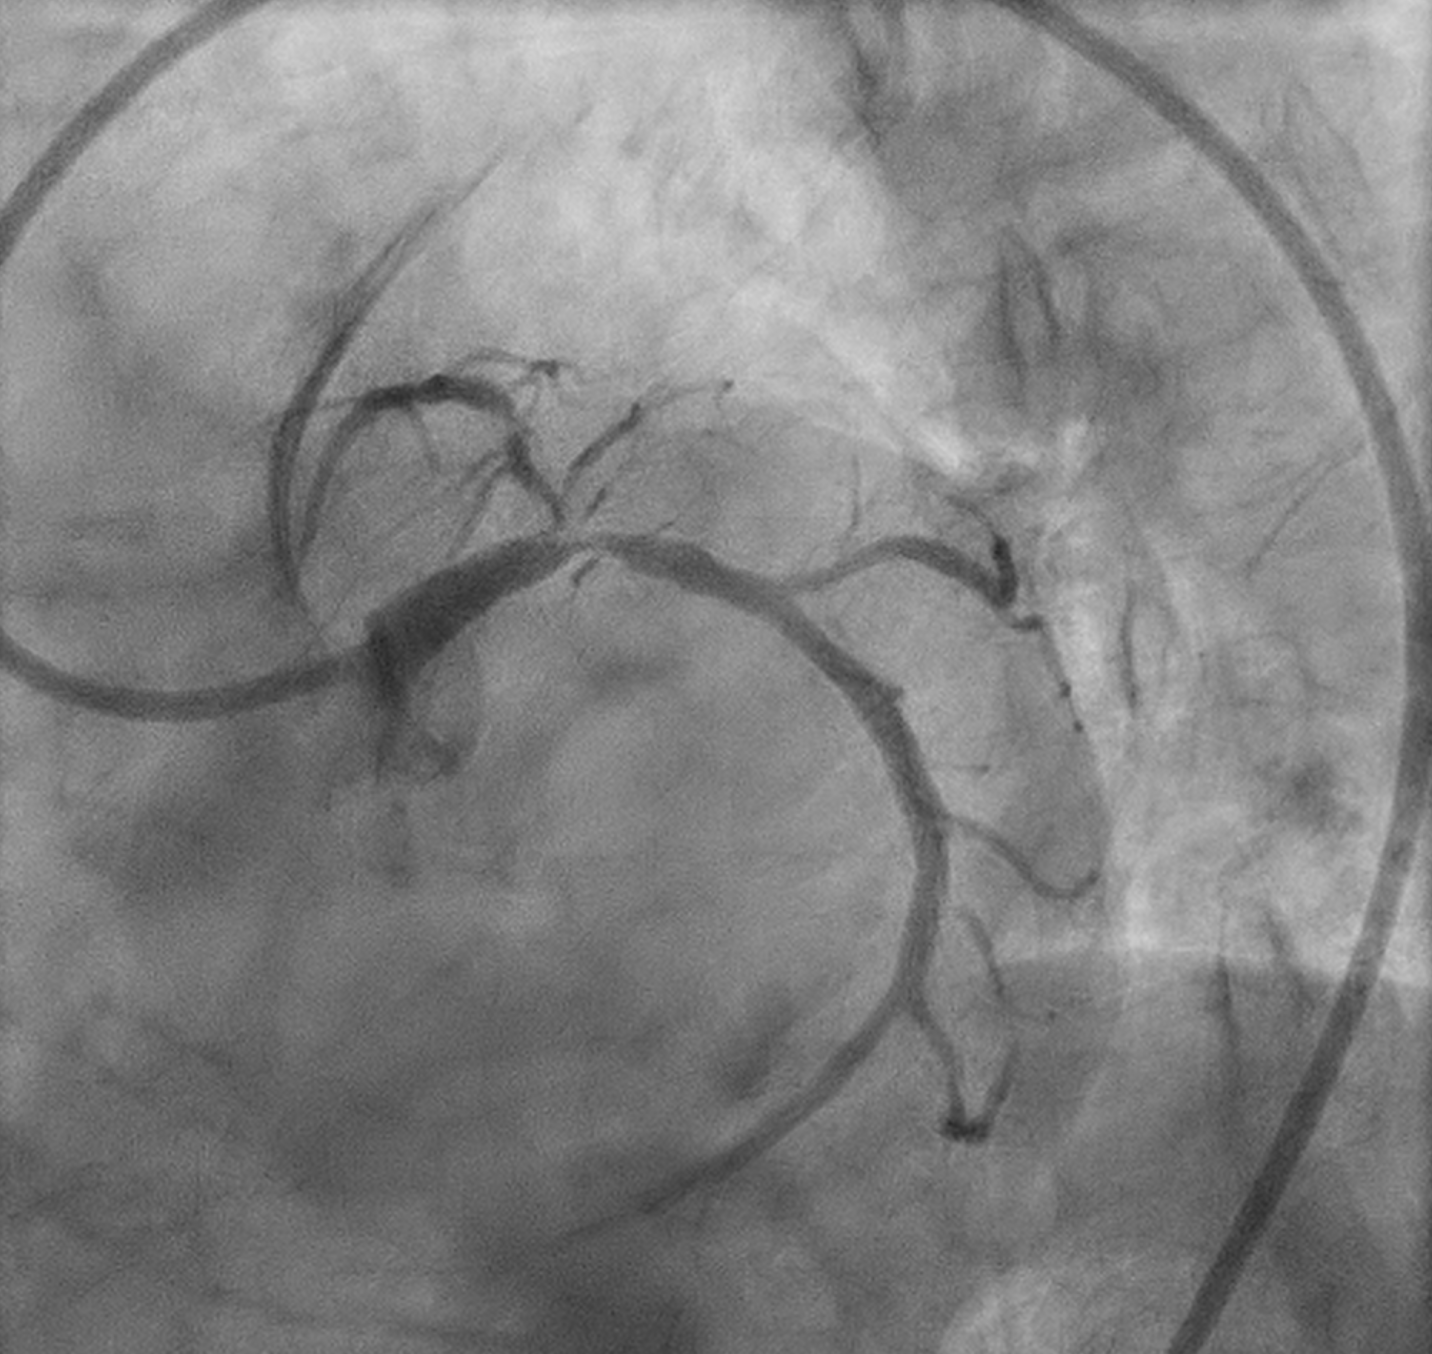

Angiography showed small non-dominant RCA with proximal severe stenosis, Left Main with severe tubular calcified stenosis at distal segmen, bifurcation lesion (medina1-1-1), LAD with diffuse calcified subtotal stenosis from ostial–mid, and LCX iwth severe tubular calcified stenosis at ostial.

A second stent (Promus Premier 2.75 ¡¿ 24 mm) was implanted in proximal–mid LAD overlaping with previous stent, then high-pressure post-dilatation and POT (NC 4.5¡¿8 mm) was performed. LCx was rewired and treated with TAP stenting (Promus Premier 3.5 ¡¿ 18 mm) after sequential and final kissing balloon dilatations. Post-IVUS confirmed well-expanded and well-apposed stents (MSA LAD 5.22 mm©÷; LCx 7.82 mm©÷).

Final angiogram showed TIMI 3 flow with no residual dissection. Procedure duration 30:52 min; contrast 180 mL; DAP 117.05 Gy¡¤cm©÷.